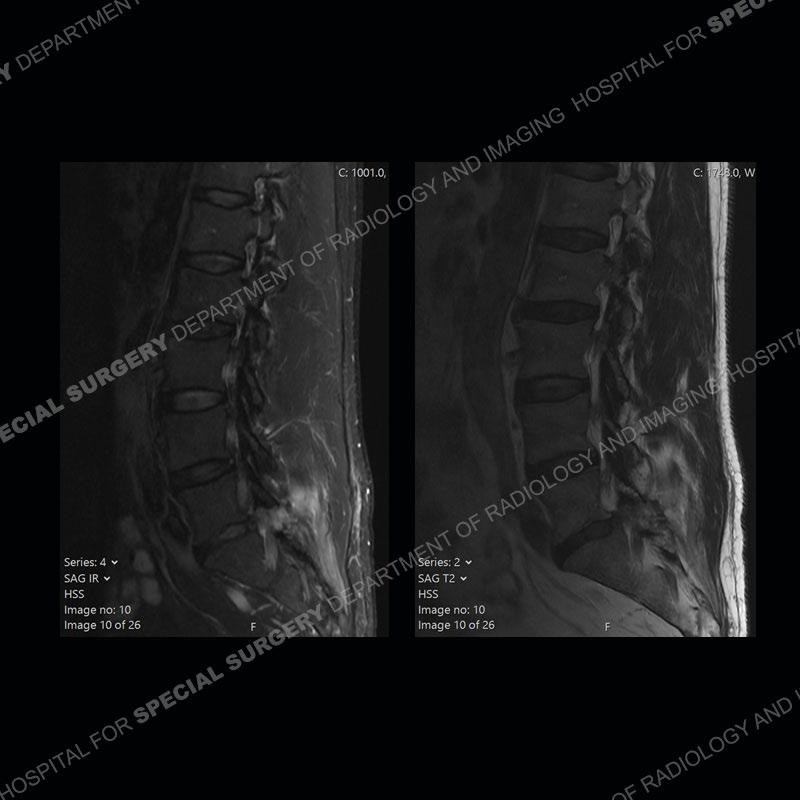

Post operative changes are seen on the left side at L5-S1 where there is near complete removal of the left sided L5 lamina, partial resection of the left L5-S1 facet joint, and resection of the left sided ligamentum flavum. In the anterolateral epidural space about the subarticular recess is a mass that demonstrates similar T1 and T2 signal characteristics to the adjacent degenerated disc. There is enhancement about the periphery of the mass, but the majority of this somewhat geographic or polyploid mass demonstrates no enhancement. The mass exerts prominent mass effect on the left S1 axillary sleeve/proximal nerve root. The left S1 nerve root shows enlargement and increased enhancement as compared to the contralateral right side.